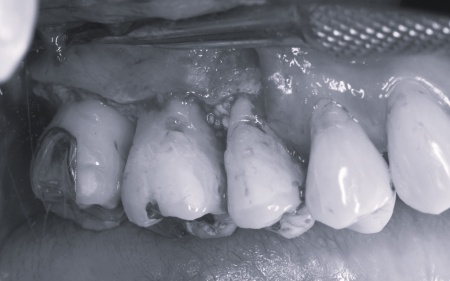

拝見したところ、上下左右の奥歯計8本(第1大臼歯、第2大臼歯)に重度の歯周病が認められました。

特に下の奥歯2本(左右第1大臼歯)は歯を支えている骨が著しく減少して歯が大きく揺れており、治療して温存することは難しい状態でした。

また、左上の奥歯(第1大臼歯)は過去に詰め物で治療されていましたが、その下で虫歯が再発しています。

まず、歯周基本治療から開始しました。

その後、状態を確認しながら外科処置を段階的に進めます。

下左右の第1大臼歯を抜歯し、その部位にインプラントを埋め込む手術を行いました。同時に、インプラントの隣にある下の第2大臼歯に対して歯周組織再生療法を施しています。

上左右の奥歯についても歯周組織再生療法を行い、歯をできるだけ残せるよう治療を進めました。